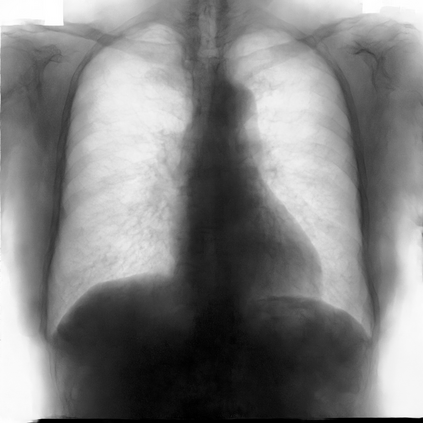

Multi-organ segmentation of X-ray images is of fundamental importance for computer aided diagnosis systems. However, the most advanced semantic segmentation methods rely on deep learning and require a huge amount of labeled images, which are rarely available due to both the high cost of human resources and the time required for labeling. In this paper, we present a novel multi-stage generation algorithm based on Generative Adversarial Networks (GANs) that can produce synthetic images along with their semantic labels and can be used for data augmentation. The main feature of the method is that, unlike other approaches, generation occurs in several stages, which simplifies the procedure and allows it to be used on very small datasets. The method has been evaluated on the segmentation of chest radiographic images, showing promising results. The multistage approach achieves state-of-the-art and, when very few images are used to train the GANs, outperforms the corresponding single-stage approach.